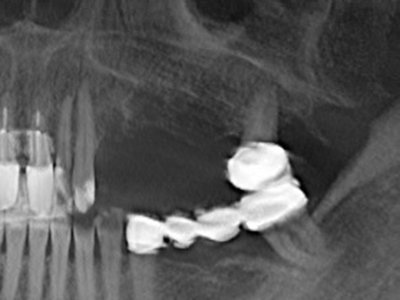

Como ya se ha demostrado en el pasado, básicamente cualquier procedimiento de cirugía de hueso representa una posible indicación para la cirugía piezoeléctrica. Así, la preparación del segmento móvil en la osteogénesis de distracción (fig. 23-25) y en la osteotomía de sándwich puede realizarse con piezas especiales, sin poner en peligro el suministro sanguíneo de la parte crestal, que resulta esencial para el éxito de ambas técnicas (González-García, Diniz-Freitas et al. 2008).

Para la extracción de implantes es posible realizar la preparación de una tapa ósea vestibular que, tras retirar el tornillo del implante, vuelve a fijarse y, de este modo, mantiene el contorno de la apófisis alveolar.

En la cirugía del seno maxilar surgen otros campos de aplicación: En este punto, tras la preparación concéntrica de una tapa ósea de la pared del seno maxilar (que suele tener forma trapezoidal), es posible eliminar patologías y cuerpos extraños del seno maxilar. La tapa ósea se repone después de finalizar la parte intra-antral de la operación y se asegura frente a una posible dislocación mediante cuñas o suturas adaptables.